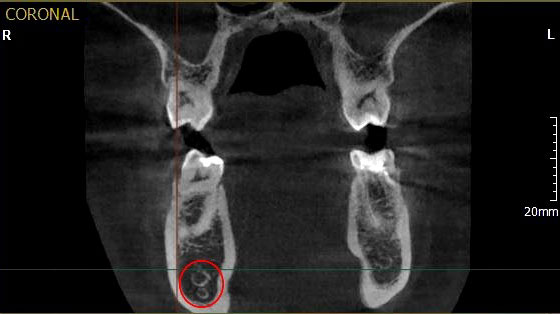

каналы стр 43

Рис. 1. Асимметричное строение нижнеальвеолярного нерва, добавочный канал в области нижней челюсти справа во фронтальной проекции конусно-лучевой компьютерной томографии от Vatech.